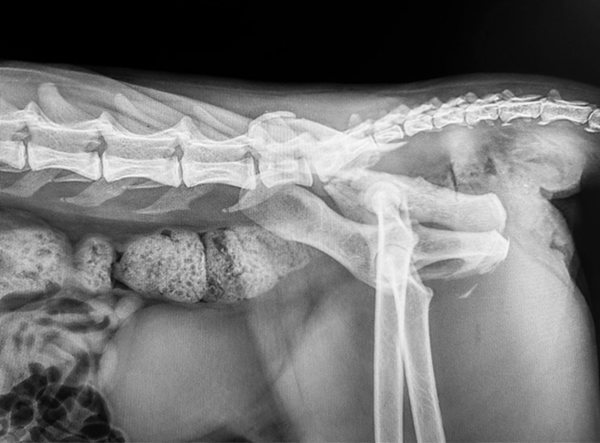

This feline patient presented with a severe pelvic trauma following high-impact trauma. Diagnostic imaging revealed a comminuted ilium and acetabulum fracture, along with sacroiliac (SI) luxation — a complex orthopedic challenge requiring careful reconstruction and stabilization.

Veterinary surgeon Dr. Matan Or (Israel) performed the repair using components from the LeiLOX 1.5 Locking Plate System, known for its precision, flexibility, and lightweight titanium construction.

Post-operative radiographs showed excellent alignment, secure implant positioning, and stable SI fixation. This multifaceted repair highlights the versatility of the LeiLOX system and the skill of the surgical team. The patient is recovering well with a positive long-term prognosis.